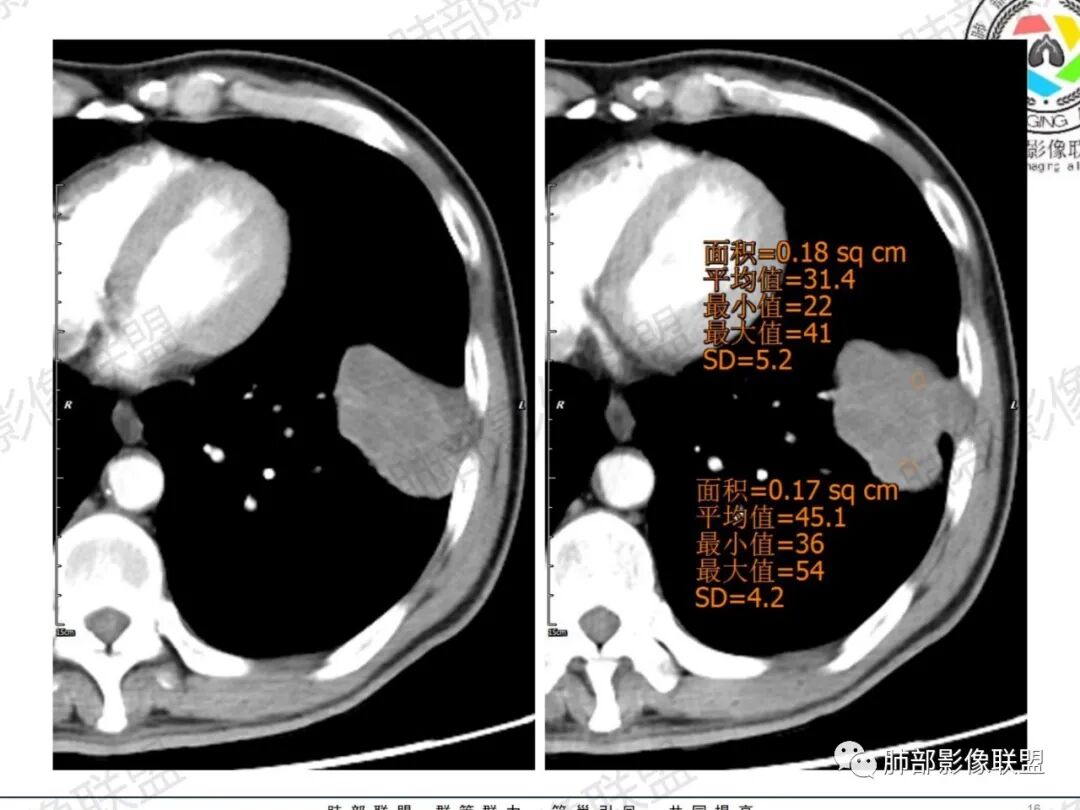

傅昌瑜:中老年男性,肺气肿背景,右胸背疼痛1周。CEA、NSE、CYFRA—211升高。左上肺混合磨玻璃结节,内见较多空泡和扩张支气管。左下肺胸膜下肿块,边缘较光滑,深分叶,似有血管进入,与支气管关系不清,内见不均匀强化,见沼泽地样坏死,有胸膜栽赃。另两肺多发圆形小结节。考虑恶性并肺内转移,多原发可能性大,左上肺腺癌,左下肺病理难以判断,小细胞癌?鳞癌?

小锁:中老年男性,肺气肿背景,右胸背疼痛1周。CEA、NSE、CYFRA—211升高。左上肺混合磨玻璃结节,边界清楚,内见较多空泡。左下肺肿块,边缘清楚,深分叶,有血管和支气管进入,胸膜凹陷。另两肺多发圆形小结节。考虑双发原位癌,左上肺腺癌,左下肺大神泌或腺鳞癌可能,肺内转移。

蓝天白云:中年男性,肺气肿背景,左肺下叶肿块,边缘膨隆,有分叶,内有湖泊样坏死,有轻中度强化,局部胸膜栽赃,收缩力不强,周围见肺气肿征象。左肺上叶混合磨玻璃影,边界清楚,考虑都是恶性,左上肺iac,左下肺腺鳞癌,或大细胞肺癌可能。两肺多发结节,考虑转移

毛勤香:老年男性,肺气肿背景,左肺下叶肿块,分叶,边缘光滑,土豆块样,细支气管闭塞,增强轻度不均匀强化,似有坏死,左肺另见多发结节,淋巴结未见明显肿大,恶性确定,吸烟史,鳞癌破坏力强,侵袭力差,多原发的一般很少多于3个,故排后,首先考虑神经内分泌癌,局部血管穿行,鉴别淋巴瘤

周太狼:中年男性,吸烟、高血压史,肿瘤指标升高,肺气肿背景下,左肺下叶肿块影,分叶、膨隆、未跨叶裂,支气管截断,不均匀强化。另双肺多发结节及磨玻璃影,左肺上叶混合磨玻璃,内可见多发空泡影。整体考虑恶性,肺癌伴肺内转移,左下肺鳞癌?神经内分泌癌?左肺上叶囊腔腺癌?

LCNEC最常见的影像特征包括:(1)肿块发生部位:周围型肺癌为主,少数发生于肺中央。(2)肿块大小及形态。因肿瘤细胞生长迅速常形成较大肿块,因此其体积一般较大,直径常在3~10cm范围内,病灶常为不规则形软组织肿块。(3)肿块边界。多数学者报道大多数肿块边界清晰,边缘呈分叶状,毛刺征及“胸膜凹陷征”少见,认为与该病对周围组织浸润较轻及较少产生纤维瘢痕组织牵拉有关联。(4)肿块密度、强化特点及代谢情况。据文献报道,该类肿瘤因体积较大CT上常见软组织肿块,且多数密度不均匀,内见囊变坏死区,增强后呈轻或中度不均匀强化(可见强化者占75.7%),认为其强化特点与其内部肉眼可见坏死灶和肿瘤较大直径有关。(5)伴随症状及远处转移。该病恶性程度高,侵袭性强,常侵犯邻近结构,如胸膜、心包、邻近骨质或纵隔内组织等,易出现纵隔淋巴结转移,部分发生肺内及远处转移,少数早期可出现广泛远处转移。